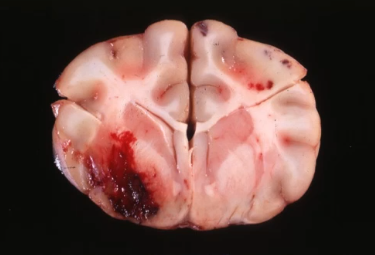

what type of hemorrhage is this?

parenchymal hemorrhage